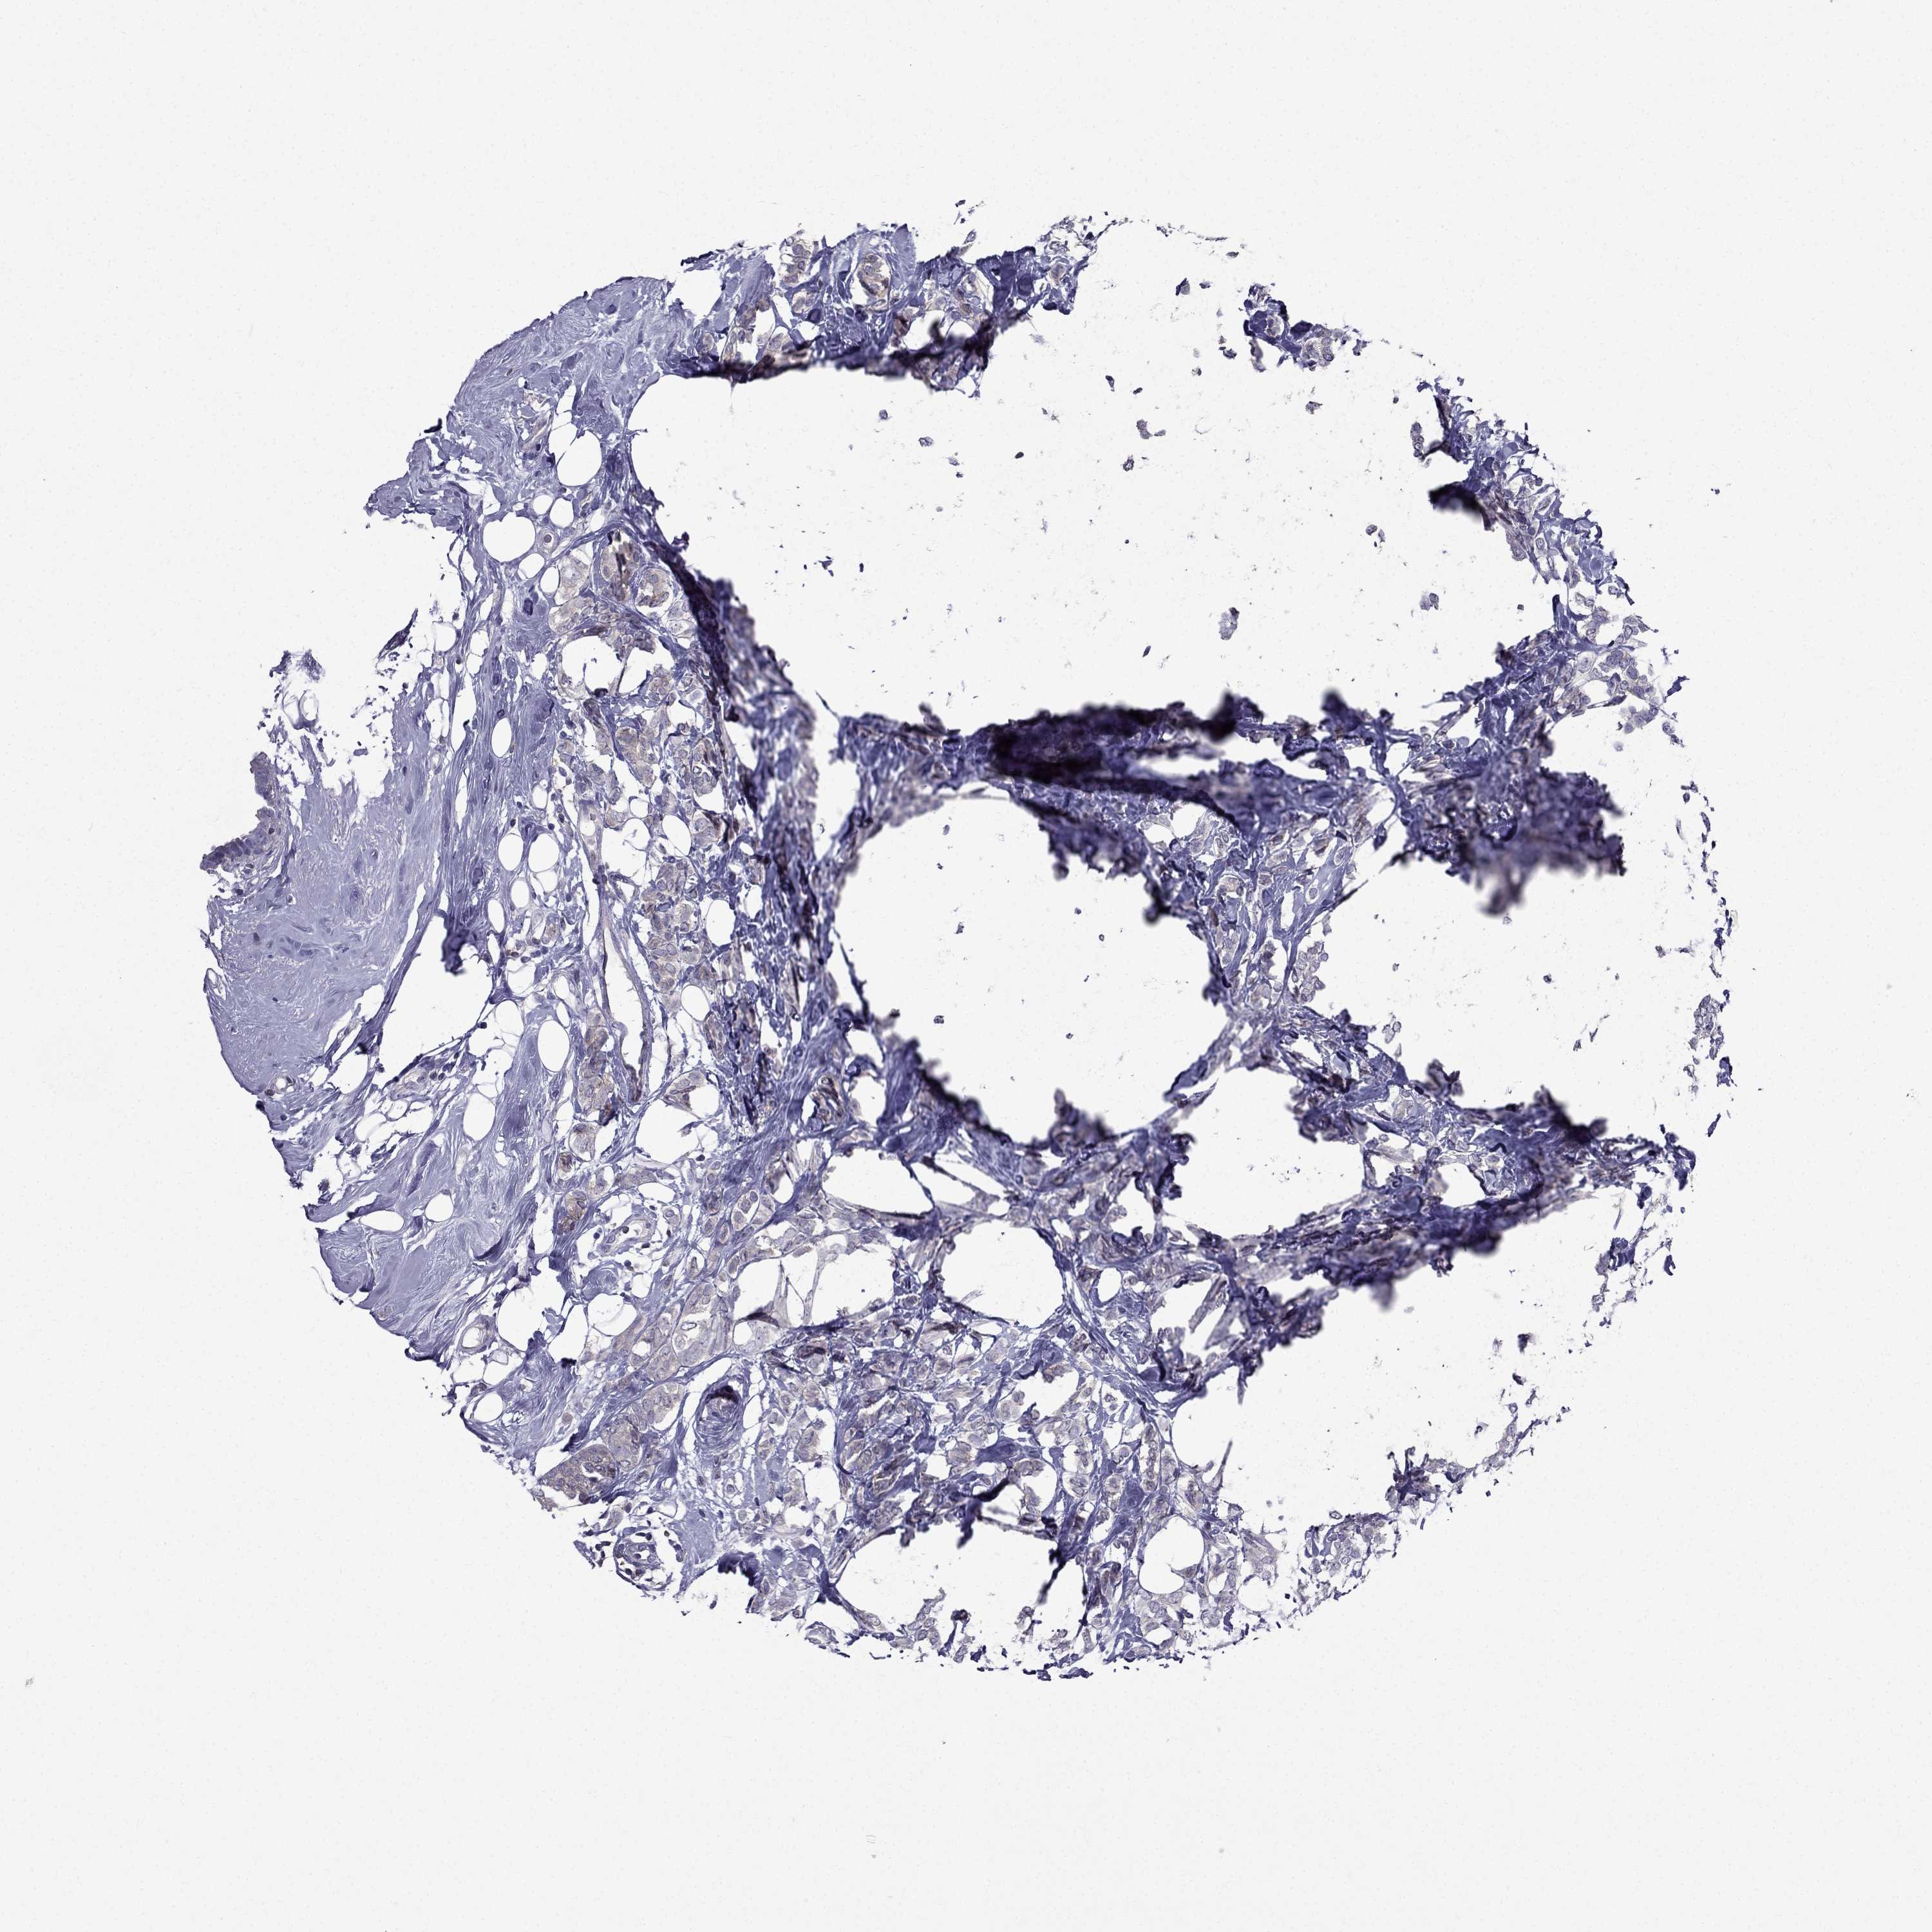

Breast cancer

Human cancer